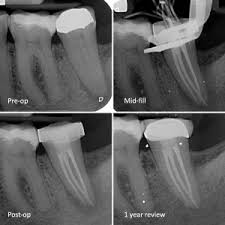

Before and After Images

Our Root Canal Treatment Experiences

Root Canal Therapy

X-rays are taken to determine the extent of the damage. Local anesthesia is administered to numb the area.An opening is made in the crown of the tooth to access the pulp.The infected or damaged pulp is removed, and the root canals are cleaned and shaped The cleaned canals are filled with a biocompatible material, usually gutta-percha.